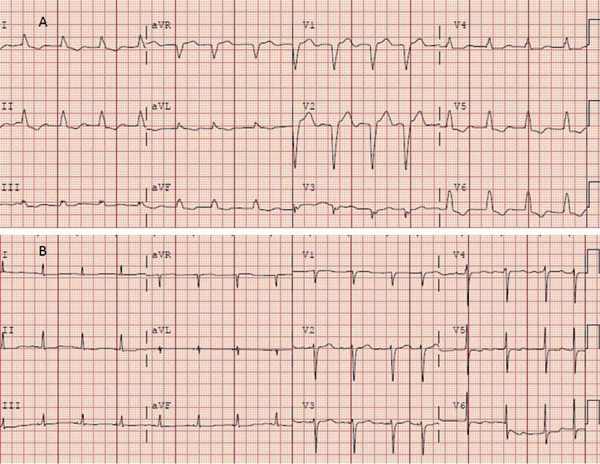

Estudios fisiopatológicos de los albores de la electrofisiología básica han sentado la base para la posibilidad de lograr el afinamiento del complejo QRS mediante MHH en pacientes con BCRI. De alguna forma, la mayoría de los pacientes con BCRI presentan un trastorno en la conducción que es longitudinal, por lo que la estimulación del haz de His puede lograr el restablecimiento de la conducción fisiológica por ambas ramas y por tanto un QRS estrecho normal o casi normal, demostrado en series de casos.

Ya han comenzado estudios que comparan MHH y TRC clásica vía seno coronario en pacientes con las indicaciones clásicas de TRC, lo que ha determinado un gran entusiasmo ante la posibilidad de lograr la resincronización en pacientes con indicación de TRC sin necesidad de ubicar un electrodo en el VI y con un procedimiento mucho más sencillo que el de TRC clásico (Figura 5) (Figura 6).

Figura 5: ECG previo (A) a la estimulación hisiana (BCRI) y posterior (B) (QRS fino). Gentileza del Dr. John Mandrola.